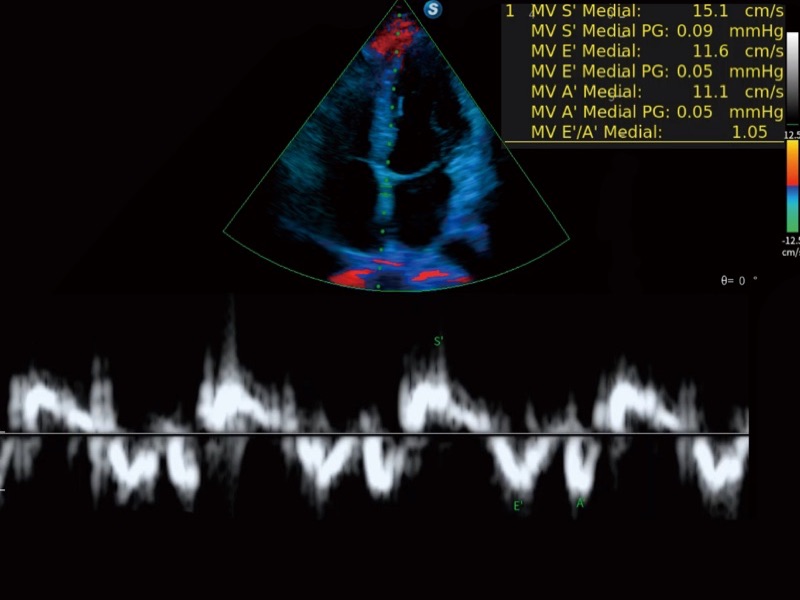

便携式彩色多普勒超声诊断系统

作为开立医疗全新打造的高端全域笔记本超声,X11集成了当前先进的硬件架构和精密的设计工艺,提升多科室临床医生在常规影像检查中的诊断能力,为临床提供全面的诊疗支持。